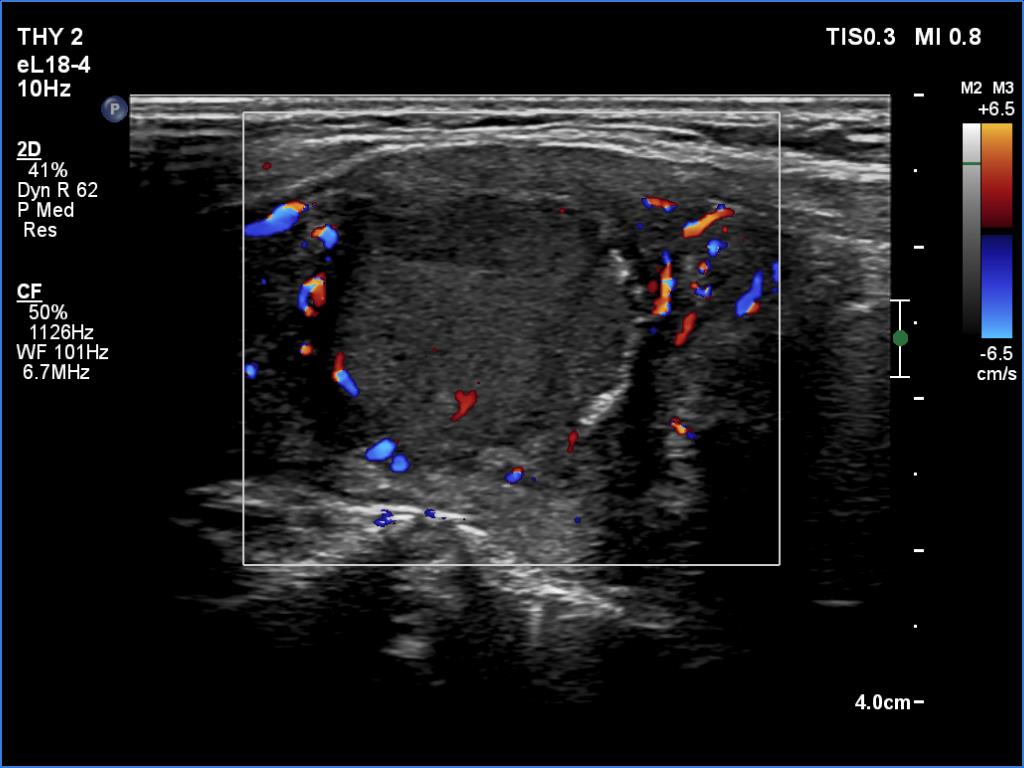

Left lobe, longitudinal view, color Doppler mode. The lesion presents perinodular blood flow.